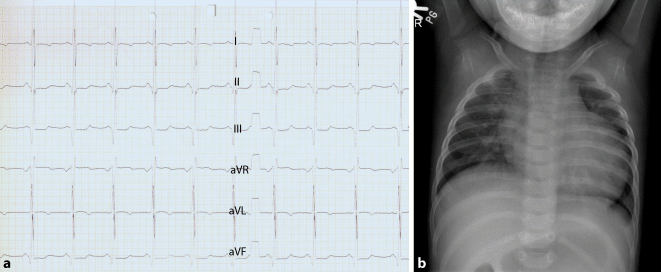

Abb. 2

Glykogenose Typ II (Morbus Pompe, lysosomale Speichererkrankung), 7 Monate alter Patient. Routinelabor ergab erhöhte Kreatinkinasekonzentration. Charakteristisches Elektrokardiogramm (50 mm/s und 10 mm/mV; verkürzte PQ-Zeit, ausgeprägte linksventrikulare Hypertrophiezeichen); Thoraxröntgenbild mit ausgeprägter Kardiomegalie und -pathie. Bei M. Pompe kann erhöhte Kreatinkinasekonzentration hinweisend sein. Für M. Pompe steht seit 2006 eine Enzymersatztherapie zur Verfügung (© D. Karall)